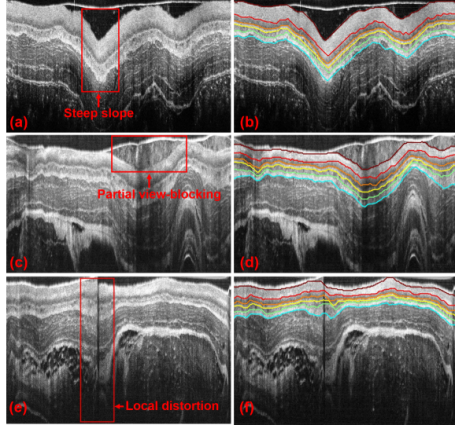

特殊成像条件下的图像分析与组织的分层提取

活体组织分层着色及内窥重建